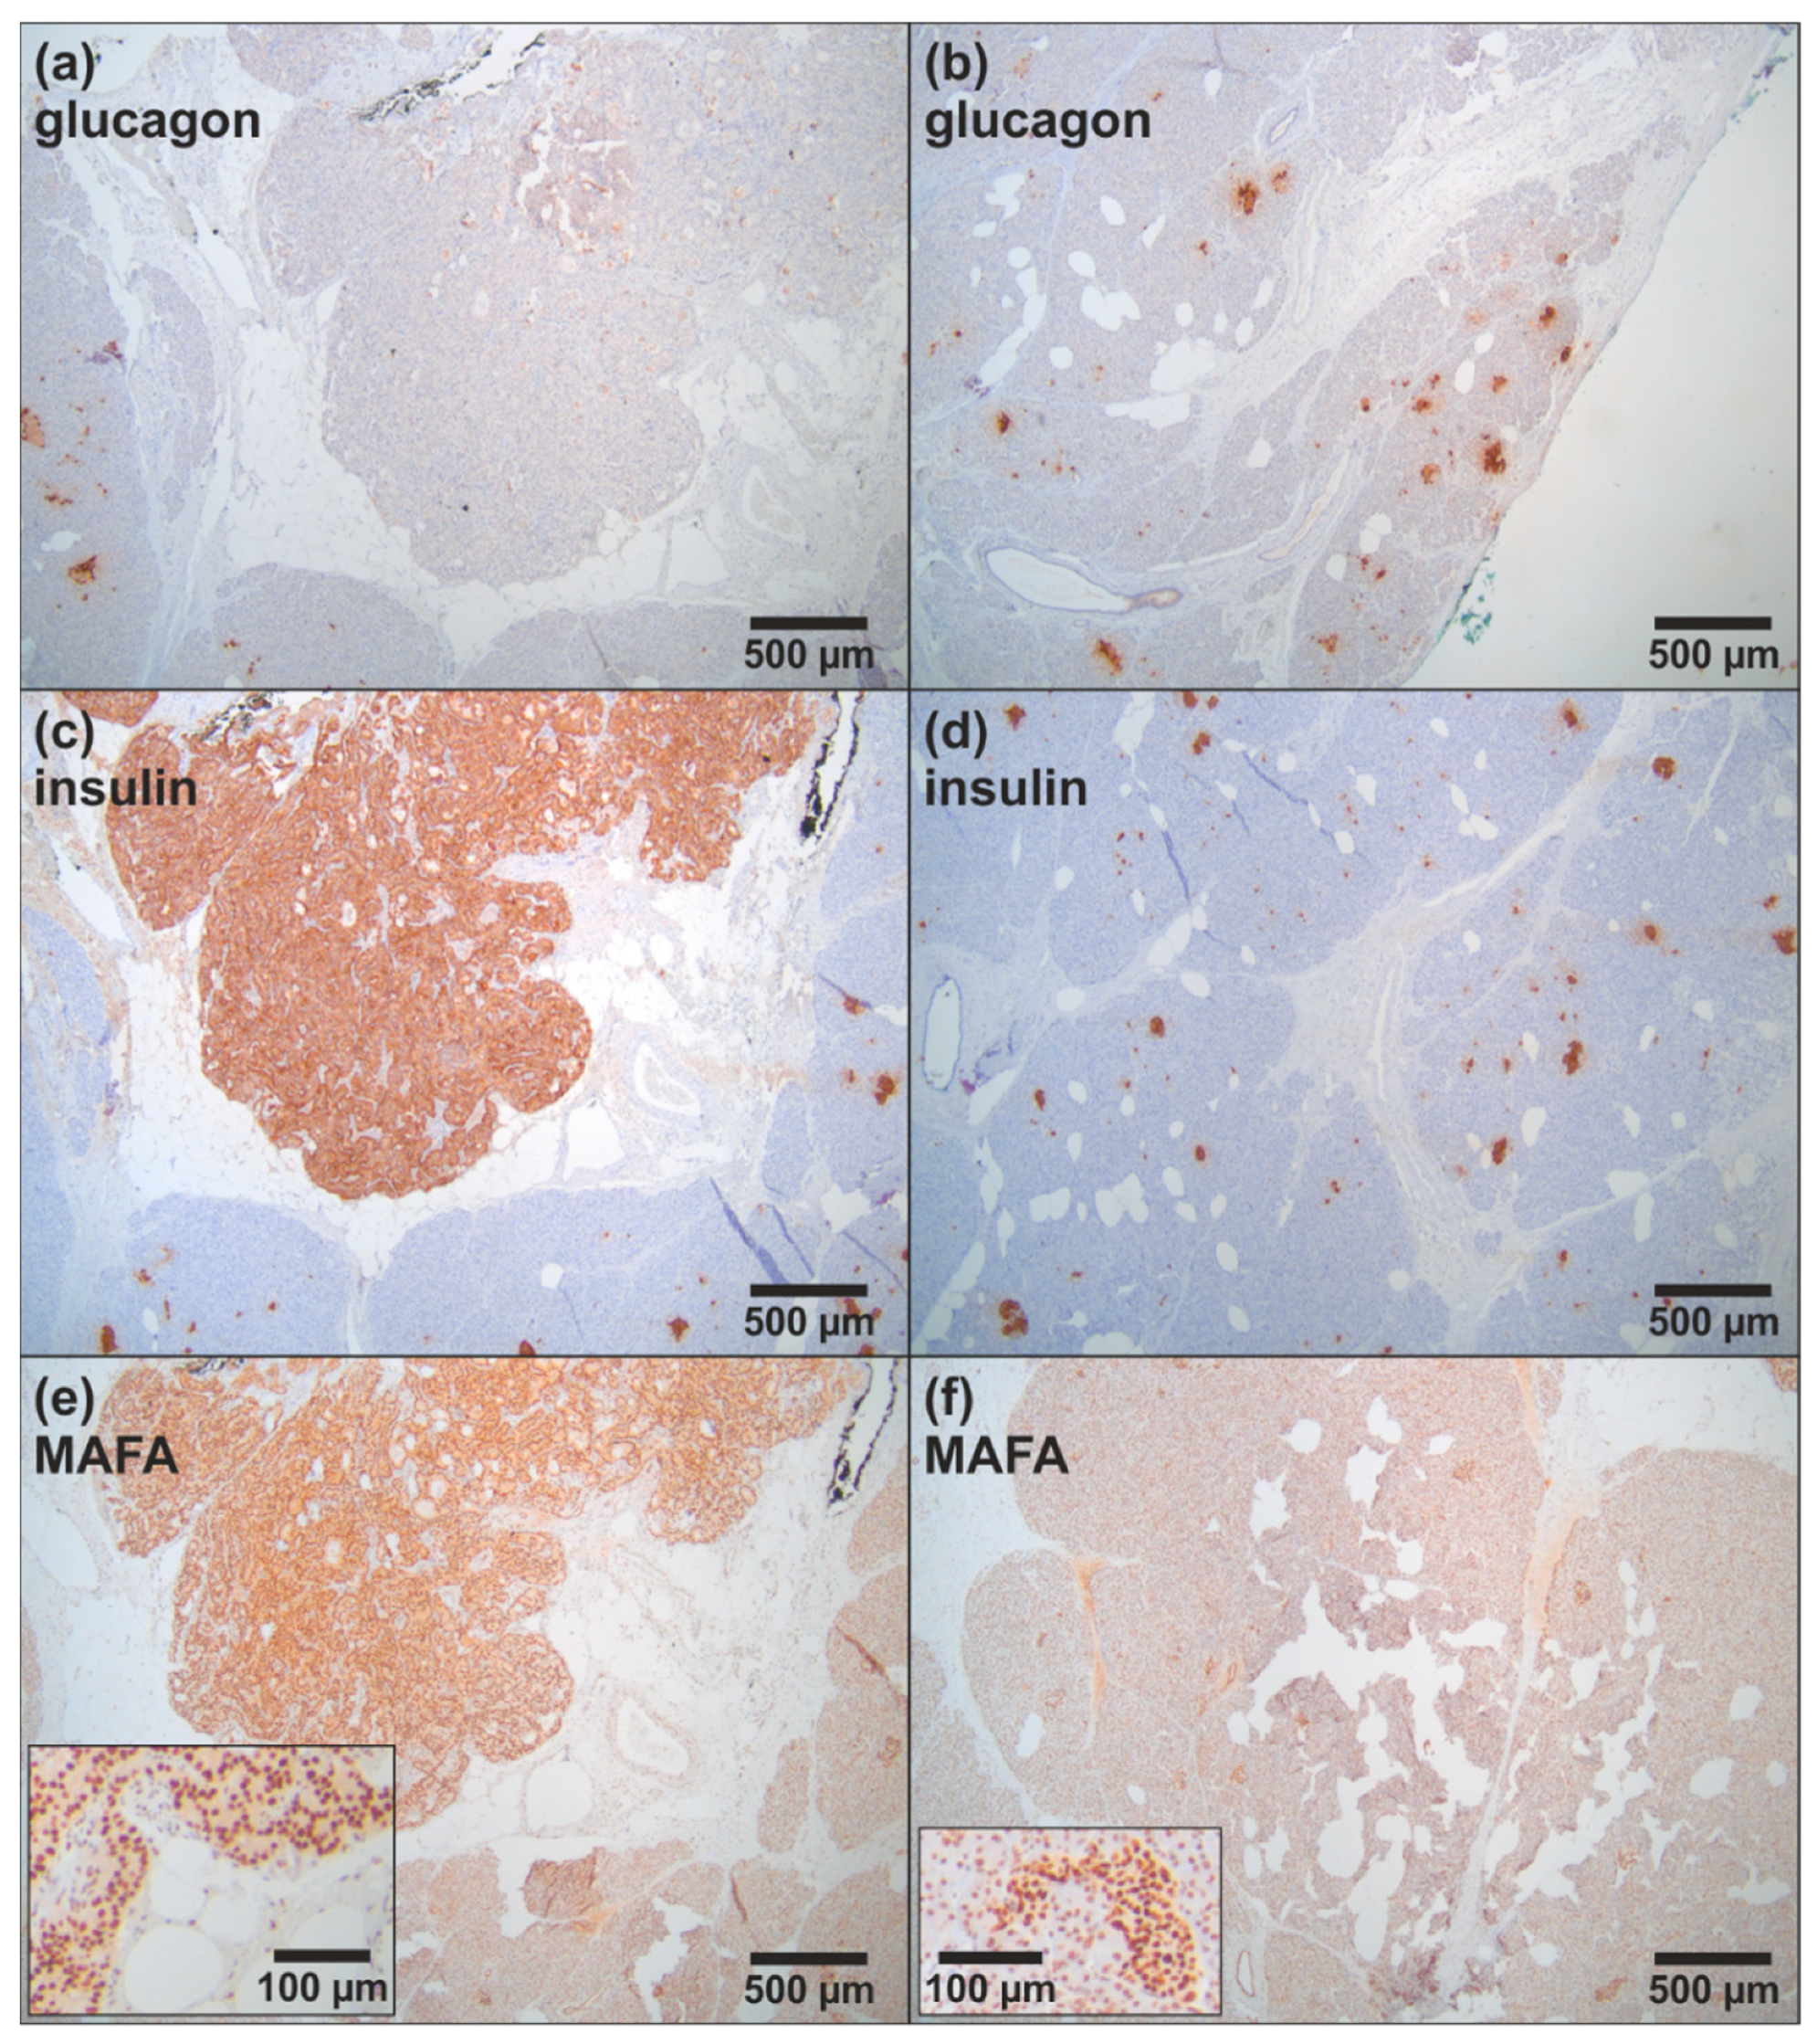

2.3. Histopathology and Immunohistochemistry

3.1.1. Clinical Case 1; Index Patient (Female, IV4, 48 Years Old at Time of Study)

3.1.2. Clinical Case 2; Sister of Clinical Case 1 (IV3, 57 Years Old at Time of Study)

4. Discussion